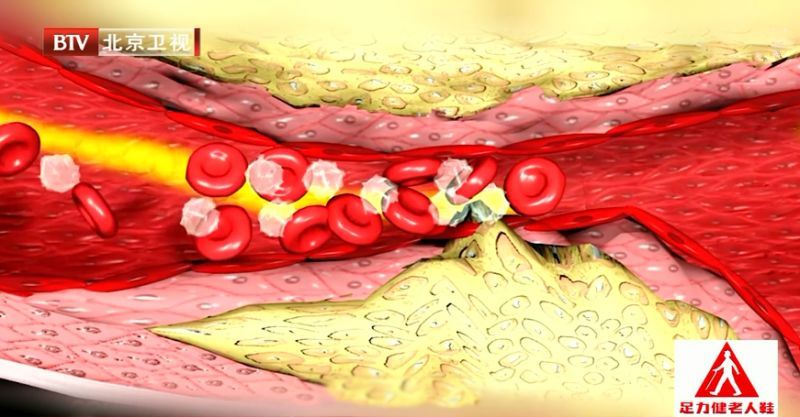

在血液流动过程中,细小沉的血脂(低密度脂蛋白胆固醇)容易沉积在血管壁,松软的血脂(高密度值蛋白胆固醇)不容易沉积。虽然血管也会收缩,把血液往前推,但心脏是推动血液在血管里流动的原动力,所以血流越接近远端小血管,流速越慢。一旦血管变窄,血流速度又慢,远端细胞得到的血就越少,会出现血供不足的情况。

血脂堵住血管,整个心肌细胞处于缺血缺氧状态,心肌功能衰减到一定程度就很难完成正常的收缩功能。心肌变薄,收缩能力下降,再出现急性的大血管的堵塞,就是一大片面积的心肌坏死,心肌细胞一旦坏死不能再生。

专家告诉我们,心衰是缺血性心肌病,小的毛细血管堵塞导致最后实际供应到细胞的那个血管没有血液了;心梗和脑梗是大血管堵了,主干堵塞,远端所有血管都没有血液供应,坏死的面积更大,很容易出现心脑血管急性事件。